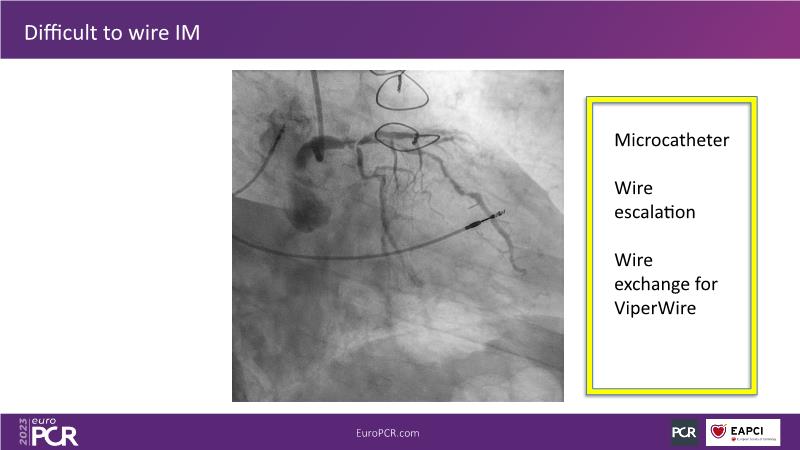

The aim of this session is to address the question of how to optimise outcomes for high-risk patients by analyzing two real-life cases for discussion: a distal calcified left main trifurcation and a high-risk PCI with orbital atherectomy.

- To learn how the distinct attributes of orbital atherectomy (OA) may help you address challenges in heavily calcified vessels